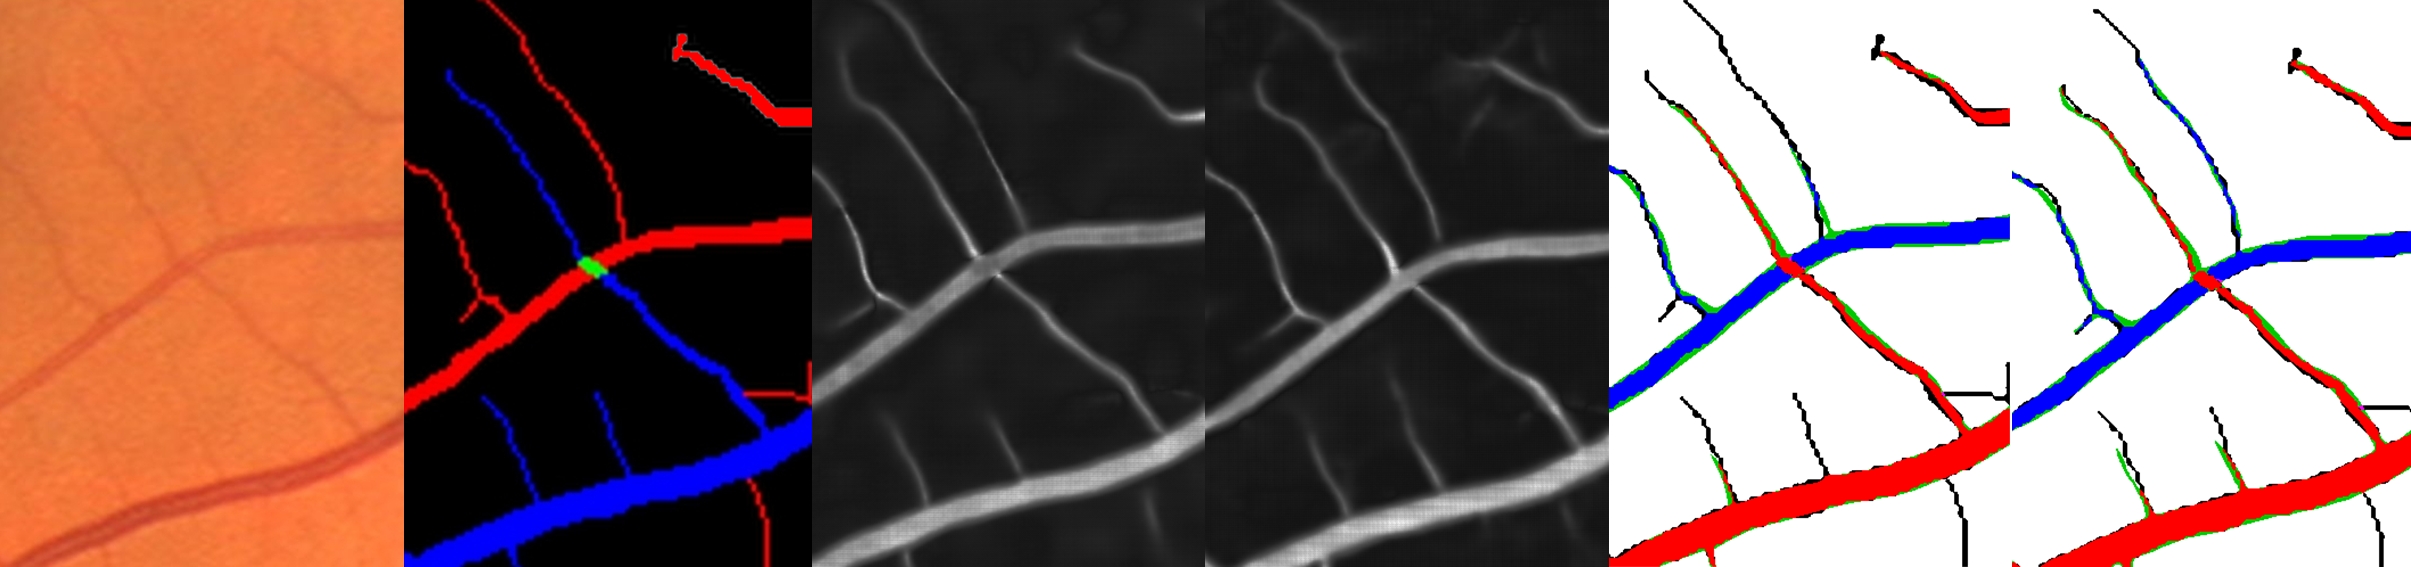

Refer to caption

Figure 4: Likelihood score propagation (LSP): a) fundus image; b) CNN output ; c) connected components; d) corresponding minimum spanning tree with node scores (from blue for veins to red for arteries) and edge costs (high cost and low propagation = thin line, low cost and high propagation = large line); e) minimum spanning tree after the first iteration; f) minimum spanning tree after the second iteration g) final classification of vessels.

This entire procedure is repeated until convergence or for a sufficient number of iterations. This allows some nodes to be reconnected properly in the minimum spanning tree so that they can receive the appropriate score propagation (for example the node b in Fig. 4 f)). Experimentally, we found that two iterations were usually sufficient to reach convergence.

Finally, the labeling of the vessel segmentation is updated according to the branches’ final scores sifinsuperscriptsubscript𝑠𝑖𝑓𝑖𝑛s_{i}^{fin}. The branch is labeled as a vein if sifinsuperscriptsubscript𝑠𝑖𝑓𝑖𝑛s_{i}^{fin} is negative and as an artery if sifinsuperscriptsubscript𝑠𝑖𝑓𝑖𝑛s_{i}^{fin} is positive (see Fig. 4 g)).